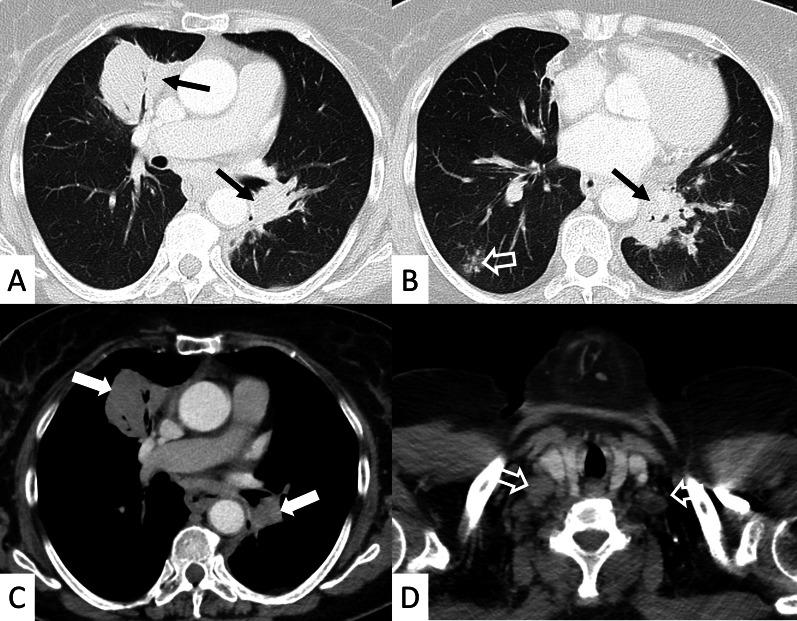

Connective tissue diseases (CTDs) include a spectrum of disorders that affect the connective tissue of the human body; they include autoimmune disorders characterized by immune-mediated chronic inflammation and the development of fibrosis. Lung involvement can be misdiagnosed, since pulmonary alterations preceded osteo-articular manifestations only in 20% of cases and they have no clear clinical findings in the early phases. All pulmonary structures may be interested: pulmonary interstitium, airways, pleura and respiratory muscles. Among these autoimmune disorders, rheumatoid arthritis (RA) is characterized by usual interstitial pneumonia (UIP), pulmonary nodules and airway disease with air-trapping, whereas non-specific interstitial pneumonia (NSIP), pulmonary hypertension and esophageal dilatation are frequently revealed in systemic sclerosis (SSc). NSIP and organizing pneumonia (OP) may be found in patients having polymyositis (PM) and dermatomyositis (DM); in some cases, perilobular consolidations and reverse halo-sign areas may be observed. Systemic lupus erythematosus (SLE) is characterized by serositis, acute lupus pneumonitis and alveolar hemorrhage. In the Sjögren syndrome (SS), the most frequent pattern encountered on HRCT images is represented by NSIP; UIP and lymphocytic interstitial pneumonia (LIP) are reported with a lower frequency. Finally, fibrotic NSIP may be the interstitial disease observed in patients having mixed connective tissue diseases (MCTD). This pictorial review therefore aims to provide clinical features and imaging findings associated with autoimmune CTDs, in order to help radiologists, pneumologists and rheumatologists in their diagnoses and management.

结缔组织病(CTDs)包括一系列影响人体结缔组织的疾病;它们包括以免疫介导的慢性炎症和纤维化发展为特征的自身免疫性疾病。肺部受累可能会被误诊,因为肺部改变仅在20%的病例中先于骨关节炎表现出现,且在早期阶段没有明确的临床发现。所有肺部结构都可能受累:肺间质、气道、胸膜和呼吸肌。在这些自身免疫性疾病中,类风湿关节炎(RA)的特征是普通型间质性肺炎(UIP)、肺结节和伴有空气潴留的气道疾病,而系统性硬化症(SSc)常表现为非特异性间质性肺炎(NSIP)、肺动脉高压和食管扩张。NSIP和机化性肺炎(OP)可见于多发性肌炎(PM)和皮肌炎(DM)患者;在某些情况下,可观察到小叶周围实变和反晕征区域。系统性红斑狼疮(SLE)的特征是浆膜炎、急性狼疮性肺炎和肺泡出血。在干燥综合征(SS)中,HRCT图像上最常见的表现是NSIP;UIP和淋巴细胞间质性肺炎(LIP)的报道频率较低。最后,纤维化NSIP可能是混合性结缔组织病(MCTD)患者中观察到的间质性疾病。因此,本图像综述旨在提供与自身免疫性CTDs相关的临床特征和影像学表现,以帮助放射科医生、呼吸科医生和风湿病科医生进行诊断和管理。